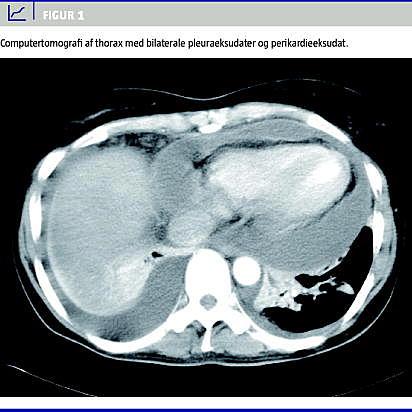

Ekkografi viste normal funktion af hjertet, men et perikardieeksudat på tre centimeter, der ikke var hæmodynamisk betydende. Computertomografi (CT) af thorax bekræftede fund af bilaterale pleuraeksudater samt perikardieeksudat. Der var ingen rumopfyldende processer eller tumorsuspekte forandringer (Figur 1 ).

Vores patient havde ledsagende perikardieeksudat, hvilket kun er beskrevet en gang tidligere i litteraturen ved syndromet [3]. Patogenesen til perikardieeksudatet er formentlig den samme som til ascitesdannelsen og pleuraeksudatet [3].